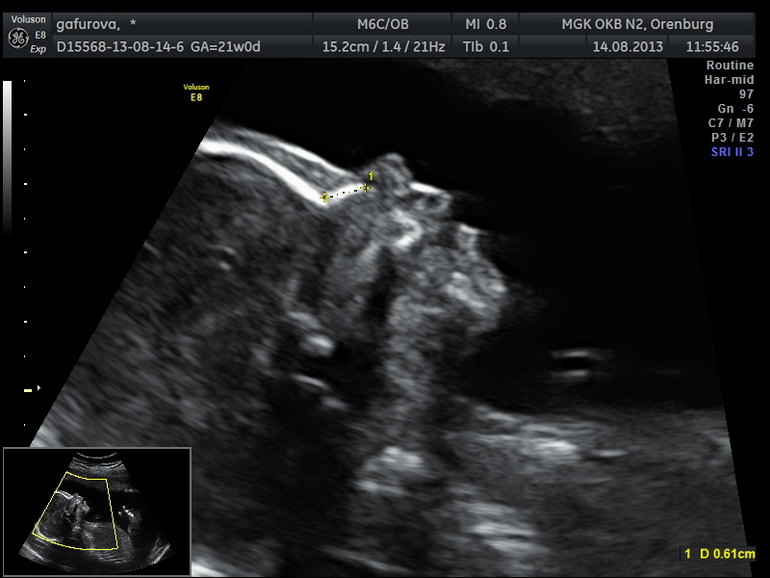

Была ужасно перепугана таким исходом,хотя по узи нам сказали,что все в норме. Вчера мы ездили в Оренбург,прошли обследование узи. Такая добрая и хорошая тетенька нас принимала. Она рассказала все) Так приятно было) И в итоге....тадАААААм..... у нас все замечательно и никаких патологий в развитии не обнаружено

вот и заключение с узи прикладываю. Кстати генетик даже не стала со мной беседовать,не было смысла

И самое замечательное событие из вчерашнего обследования это ФОТОЧКА моей масяськи...аааааааа....выпросила....